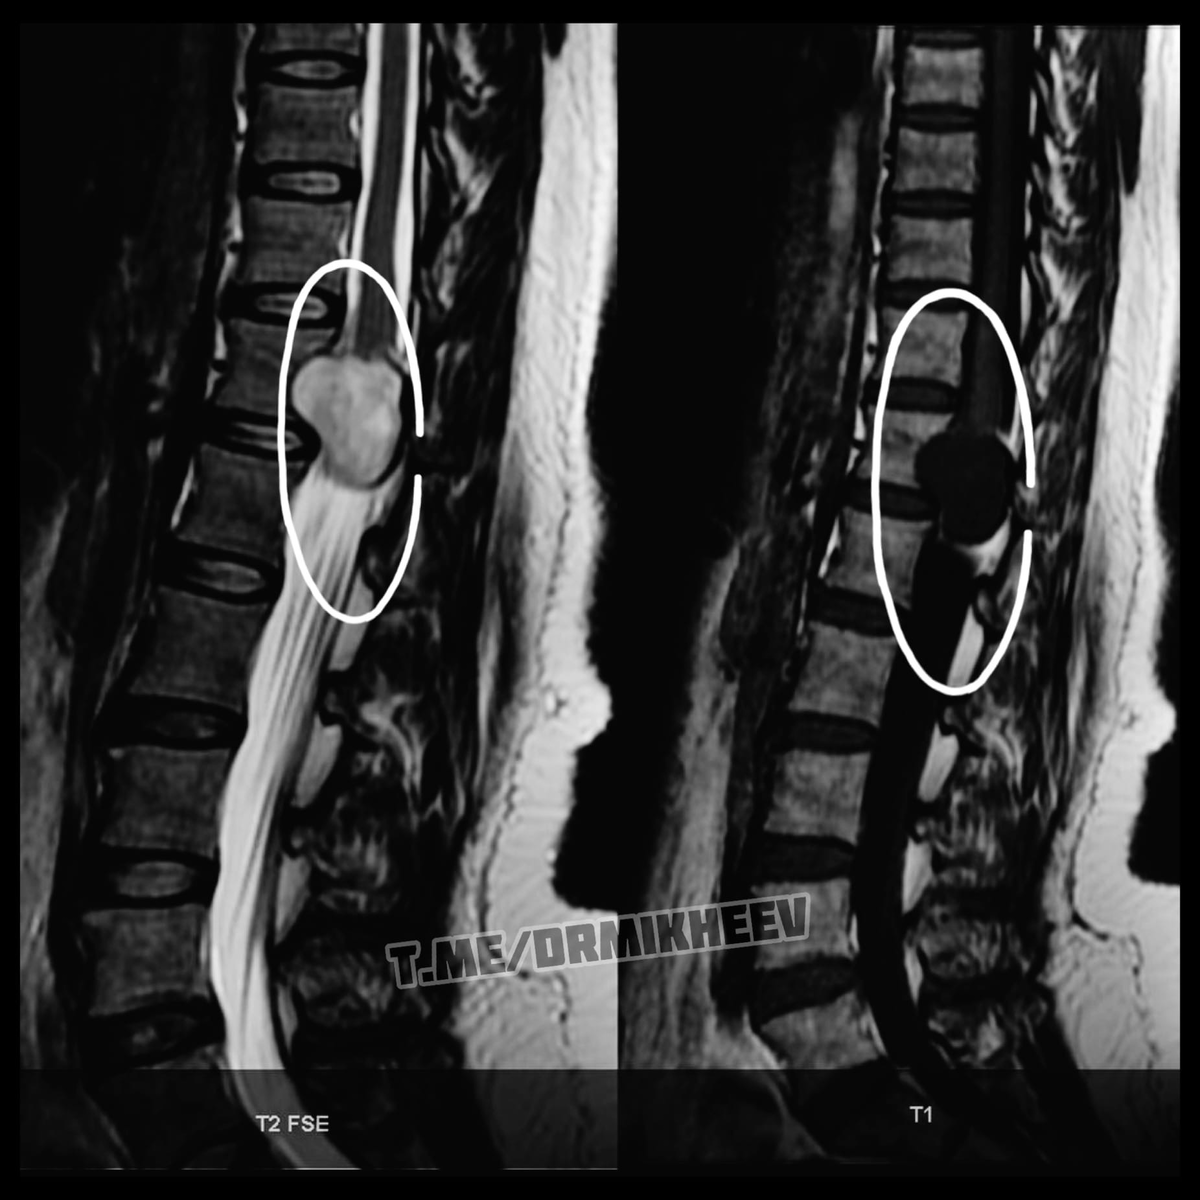

НЕВРИНОМА (шваннома)

Сегодня хочу показать пример того, почему не стоит пренебрегать МРТ, если Вам об этом говорят. Есть такая «штука», которая называется НЕВРИНОМА, или ещё как называют ШВАННОМА☝🏻 Второе название получено, потому что развивается она из шванновских клеток🌀 Это доброкачественная опухоль и развивается она достаточно медленно и долгое время не даёт о себе знать.

Вообще чаще всего ее диагностируют в шейном или грудном отделе, реже в поясничном. Рассмотрим симптоматику грудного и шейного отдела.

На фото приведены пара примеров МРТ. #ДокторМихеев